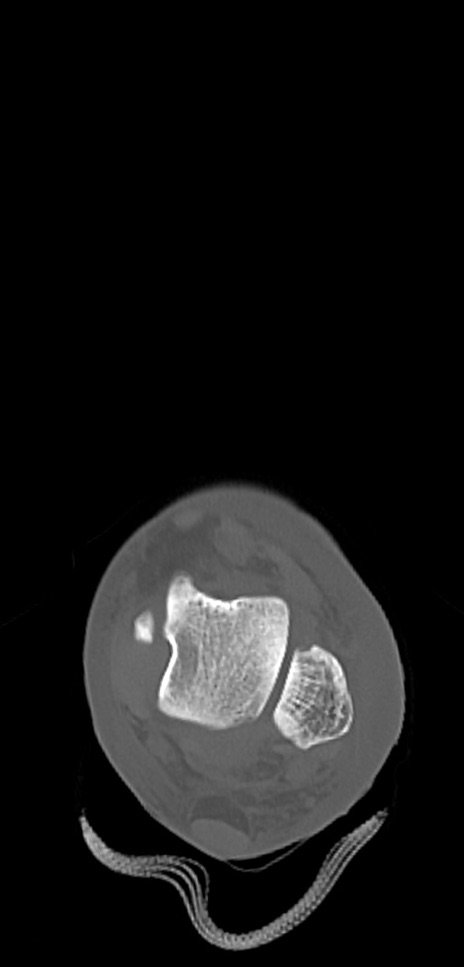

症例37 左足関節CT(横断像)

左足関節CT